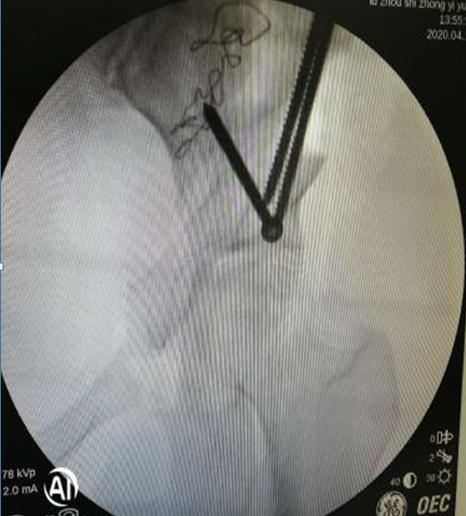

术中,左侧髋臼周围截骨

在李彬主任的带领下,肖女士进行了髋臼周围截骨术PAO保髋治疗:调整髋臼位置,使髋关节的旋转中心适度内移;增加髋臼对股骨头的覆盖,增加负重的关节面,降低了髋关节负重面软骨的应力,达到了延迟或阻断髋关节炎进展的目的,延长了自身髋关节的使用寿命。目前,患者恢复良好。